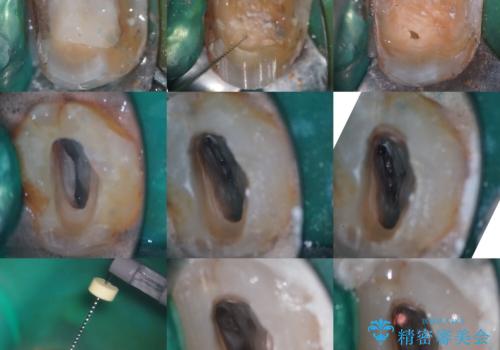

- 奥歯がズキズキ痛いことを主訴に来院されました。

検査の結果、診断を症候性不可逆性歯髄炎、症候性根尖性歯周炎とし抜髄を行っております

根管充填はhydraulic condensation techniqueにて行なっております。

シーラーはWell pulp ST 使用